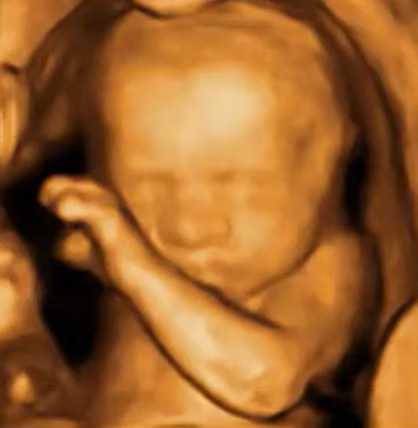

Major Upgrade: SonoStar is about to launch a series of 3D wireless handheld ultrasound devices, supporting various convex and linear array (electronic array with mechanical swing/rotary scanning) configurations. The supported frequency range is 2M-20M, with exceptionally low costs (only slightly higher than the previous 2D handheld ultrasounds).

3D imaging is widely used in obstetrics (to examine fetuses), medical aesthetics (to assess fillers), as well as in breast, thyroid, carotid, and musculoskeletal imaging.